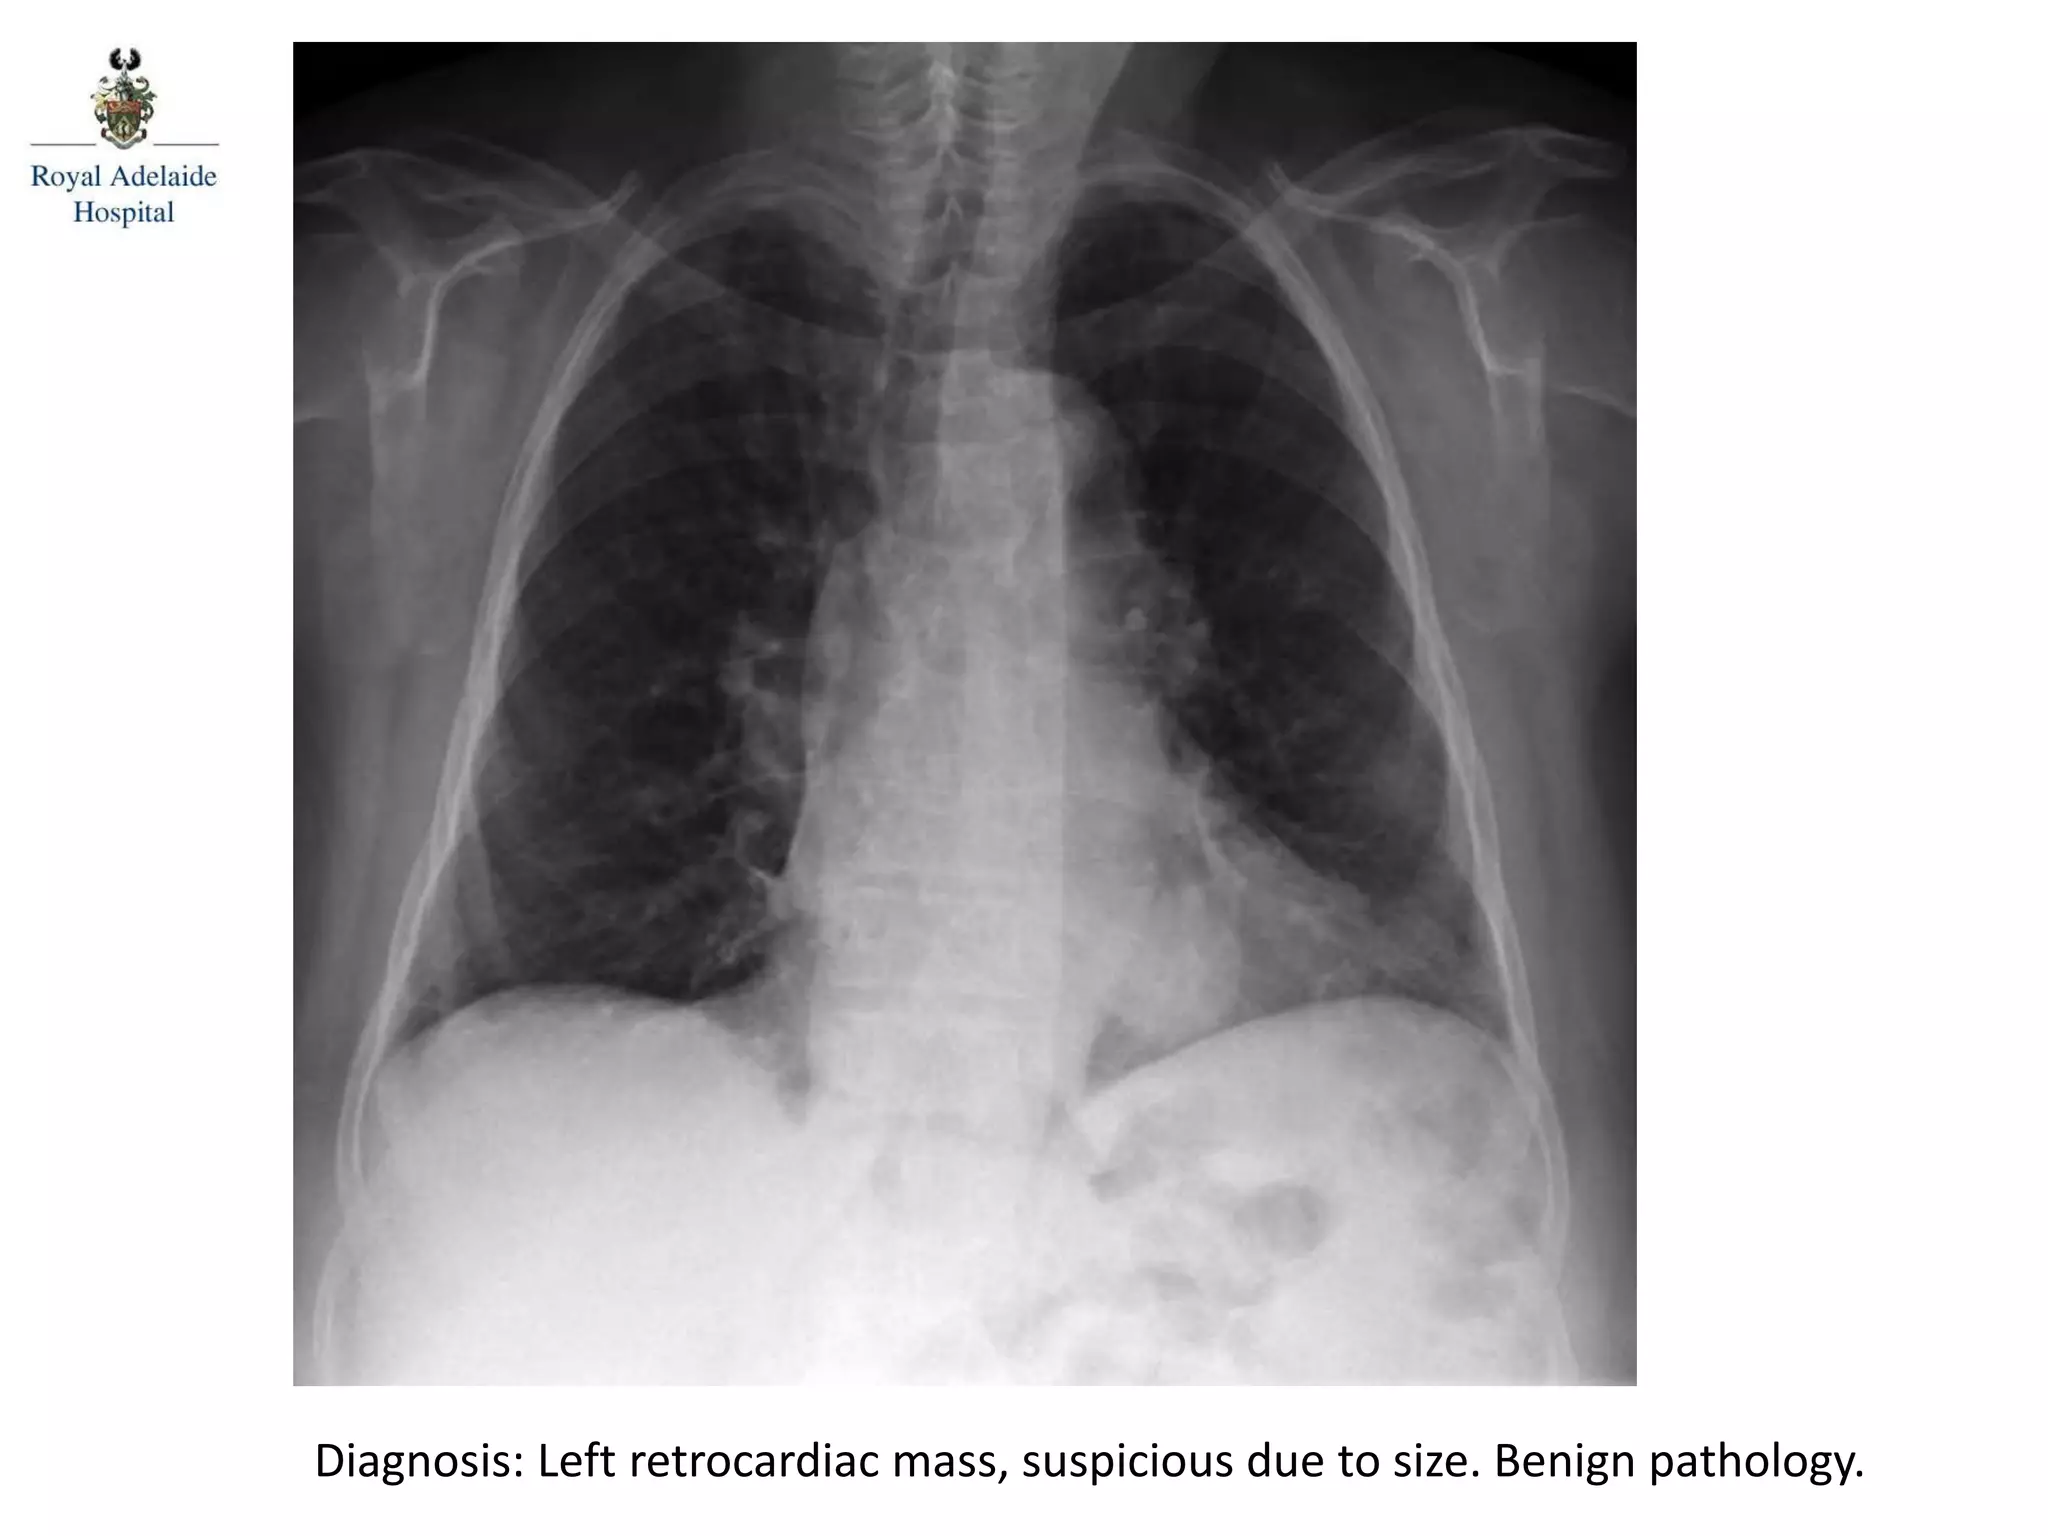

Diagnosis: Left retrocardiac mass, suspicious due to size. Benign pathology.